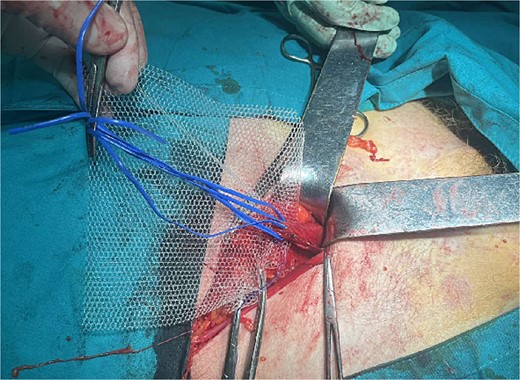

A 72-year-old patient, in good physical condition with a BMI of 26.1, came for an examination due to swelling in the right lateral abdominal wall without swelling of the scrotum. The patient was operated on for a right-sided inguinal hernia as an 8-year-old boy, but there was no appropriate medical documentation for the operative technique used. A month ago, besides the swelling, he experienced occasional abdominal pain and difficulties during physical activities in his garden. During clinical examination, a soft swelling in the right lateral abdominal wall, compressible under palpation was ascertained (Fig. 1). The abdominal ultrasound and contrast abdominal CT showed a thinned right abdominal wall with superficial intestinal loops and the differential diagnosis of a large recurrent inguinal or Spigelian hernia was presumed (Fig. 2). The patient received one dose of prophylactic cephalosporin preoperatively, and was operated on under general endotracheal anesthesia, in a supine position with a lumbar pillow placed for a slight tilt to the left. A right lateral lumbar-inguinal skin incision 4–5 cm above the anterior superior iliac spine in a horizontal direction following the lumbar dermatomal lines was performed. Subcutaneous fat was gently separated and the hernial sac dissection went to its apex below the right costal arch and base to the deep inguinal opening. When the sac was completely freed, the final diagnosis of giant recurrent indirect inguinal hernia (Fig. 3), and the sac with its content was repositioned in the abdominal cavity without opening the abdominal cavity and partial closure of the internal iliac ring was performed with resorptive sutures. After the dissection of the inguinal ligament up to the pubic tubercle (without extending the skin incision) a 15 × 12 cm polypropylene mesh was placed (Fig. 4), fixed to the pubic tuberculum and conjoint tendon with a laparoscopic taker (Fig. 5), and the ileopubic ligament partly with individual and partly with continuous non-absorbable polypropylene 2/0 suture. An opening for the spermatic cord was provided and medially the mesh was fixed with individual resorptive stitches (Fig. 6). The aponeurosis of the external oblique muscle was closed as much as it allowed to be approximated followed by individual subcutaneous and skin stitches (Fig. 7). The operating time was 65 minutes without blood loss and the patient had a quick and satisfactory recovery. He was discharged from the hospital on the third post-op day, and the skin stitches were removed on the 14th day. One month after the surgical treatment the patient was in good condition without any complaints (Fig. 8).

Placement of the polypropylene mesh 15 × 12 cm after dissection of the spermatic cord

Mesh fixation to the pubic tuberculum and conjoint tendon with a laparoscopic taker